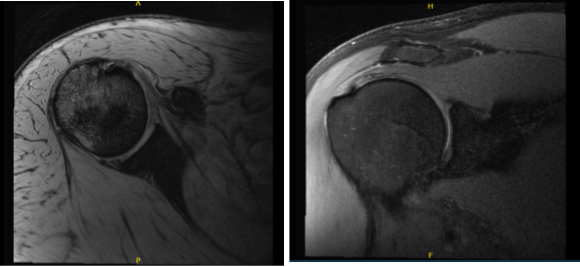

MRI were reviewed and discussed by the doctor, there is mild supraspinatus and infraspinatus tendinosis. Mild subscapularis tendinosis is present with a focal partial-thickness tear of the mid fibers.

A small lobulated hyperintense focus along the superficial margin of the subscapularis tendon likely reflects a small ganglion. The tree’s minor tendon is intact. No full-thickness rotator cuff tear is identified. No disproportionate rotator cuff muscle atrophy is present.

There is mild acromioclavicular joint arthrosis. Mild subacromial-subdeltoid bursitis is present. It showed that it has partial tearing of the rotator cuff as well as tear of the biceps tendon along with subacromial spur and AC arthritis. The biceps tendon is located within the bicipital groove.

There is mild biceps tendinosis, preferentially of its intra-articular portion, with a linear partial-thickness tear of the intra-articular portion of the bicep’s tendon extending distally to the level of the proximal bicipital groove. Minimal biceps tenosynovitis is present

There is a tear of the superior labrum which extends into the anterior superior and posterosuperior labrum. No focal chondral defect is identified over the glenohumeral joint. Trace fluid is present within the glenohumeral joint. There is no acute fracture or osteonecrosis.

Mild multifocal rotator cuff tendinosis with a focal partial-thickness tear of the subscapularis tendon. No full-thickness rotator cuff tear. Linear partial-thickness tear of the intra-articular portion of the bicep’s tendon extending distally to the level of the proximal bicipital groove, superimposed on mild tendinosis, with minimal biceps tenosynovitis.

Tear of the superior labrum which extends into the anterior superior and posterosuperior labrum. Mild acromioclavicular joint arthrosis. Mild subacromial-subdeltoid bursitis.

MRI-3T Right shoulder non-contrast